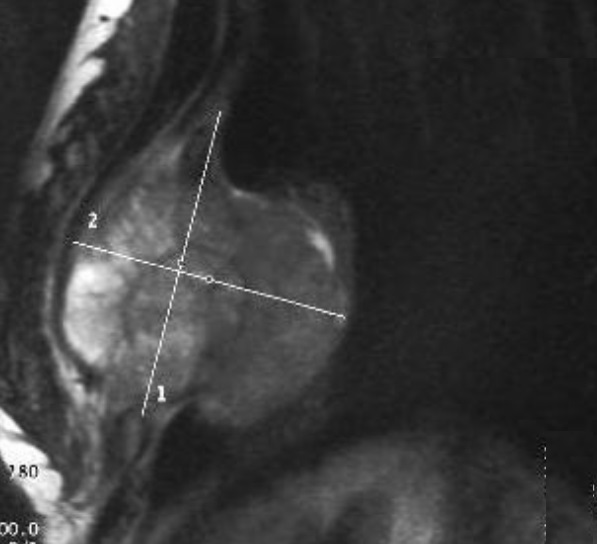

Image radiologique IRM : Aspect lesionnelle IRM est hypo à

isosignal ; rehaussement heterogene sur T1 avec Gd injection

intraveineuse ; hypersigal heterogene sur T2 avec aspect

de hyposignal en strie de cheveux du lesion